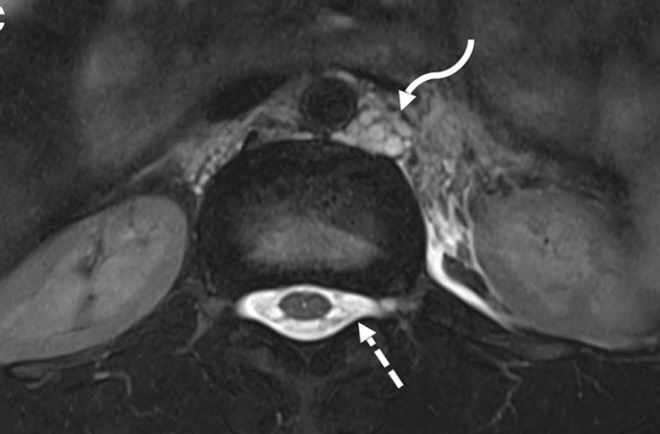

c. Lipomatose encéphalocraniocutanée (ECCL): peau, yeux, SNC)

ECCL: